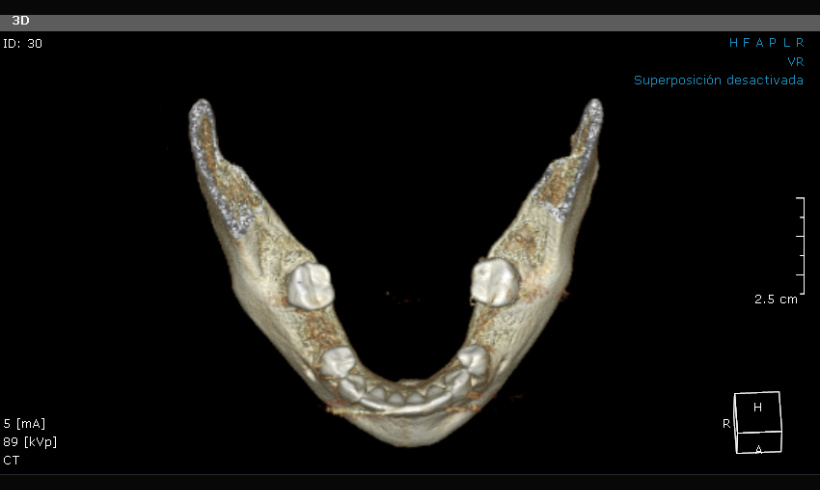

La tomografía, junto con el escaneo nos permite realizar guías quirúrgicas para la colocación de implantes, alargamiento de coronas, colocación de mini implantes de ortodoncia, tratar endodóndicamente dientes calcificados.

Tomografía para guías quirúrgicas